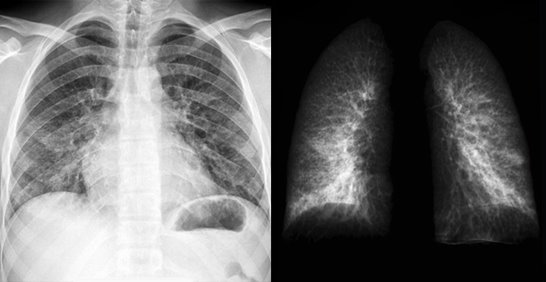

기침과 함께 흉통이 동반되는 상황을 대부분으로 많은 폐암환자들이 겪고 있는 증상입니다. 그리고 기침과 함께 동반하는 흉통이 있다고 하면 폐 엑스레이를 찍어봐야 하고, 가슴의 통증 및 흉통이 발생하는 이유는 흉막과 흉벽에 위치한 암 때문으로 보통 따끔거리는 증상이나 날카로운 것으로 찌르는 듯한 가슴통증이 있습니다. 이러한 폐암 초기증상이 있다면 참지 말고 즉시 내원하여 진찰받아 보시기 바랍니다.